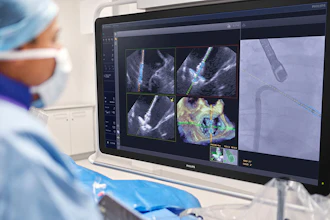

GE HealthCare aims to develop AI-enabled X-ray and ultrasound systems by using the new NVIDIA Isaac for Healthcare platform, built on NVIDIA’s three computers used to build physical AI, including NVIDIA Omniverse for robotic simulation workflows. Using the NVIDIA Cosmos platform for synthetic data generation, physics-based sensor simulation, imitation, and reinforcement learning, GE HealthCare plans to train, test, and tune autonomous ultrasound and X-ray devices in a virtual environment before deployment in the physical world.

NVIDIA and GE HealthCare will initially focus on autonomous development within X-ray systems, specifically the potential utilization of the NVIDIA Isaac for Healthcare and Jetson platforms. GE HealthCare plans to explore Isaac for Healthcare platform and synthetic data generation to simulate various scenarios. This will help to automate repetitive tasks performed by a technologist in the patient exam room. The goal is to enable care teams to focus more of their time on direct patient care and complex cases. The companies will also explore the development of machine-to-patient interactions to autonomously lead the patient through the scan journey.